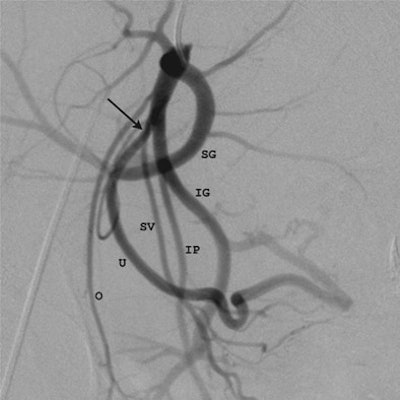

| Images in a 44-year-old woman. Above, 3D-reconstructed contrast-enhanced MR angiographic image from the pre-embolization study. The model was rotated to a 24° left obliquity for demonstration of the origin (arrow) of the right uterine artery (U) (routine oblique view). Upper right corner of the image shows the corresponding C-arm position and the obliquity angle (24° left oblique). Below, digital subtraction angiography (DSA) image in the same patient shows the corresponding angiographic projection and clear demonstration of the origin (arrow) of the right uterine artery (U). Additional arteries visualized include the common iliac (CI), external iliac (EI), inferior gluteal (IG), internal iliac (II), internal pudendal (IP), obturator (O), superior gluteal (SG), and superior vesical (SV). Both images courtesy of the Radiological Society of North America. |